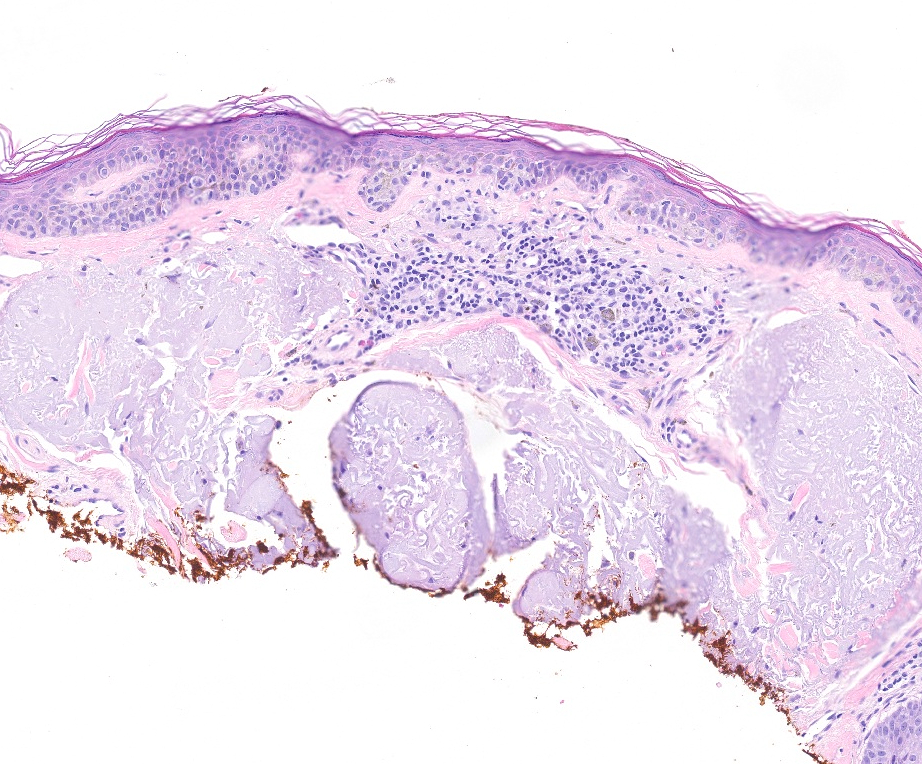

Microscopic (histologic) description

- Proliferation of intraepidermal (single and nested) melanocytes overlying solar elastosis

- Melanocytes demonstrate crowded growth along the basal epidermis

- Associated epidermal alterations, including loss (effacement) of epidermal rete and associated irregular epidermal hyperplasia

- Involvement of adnexal epithelium

- Invasive component, if present, consists of single or nested melanocytes in the dermis with similar cytologic features to those in the in situ component (Cancer Res 1969;29:705, Am J Pathol 1969;55:39)

Microscopic (histologic) images

Contributed by Joseph Gillam, M.D., Jennifer Crimmins, M.D. and Mark Mochel, M.D.